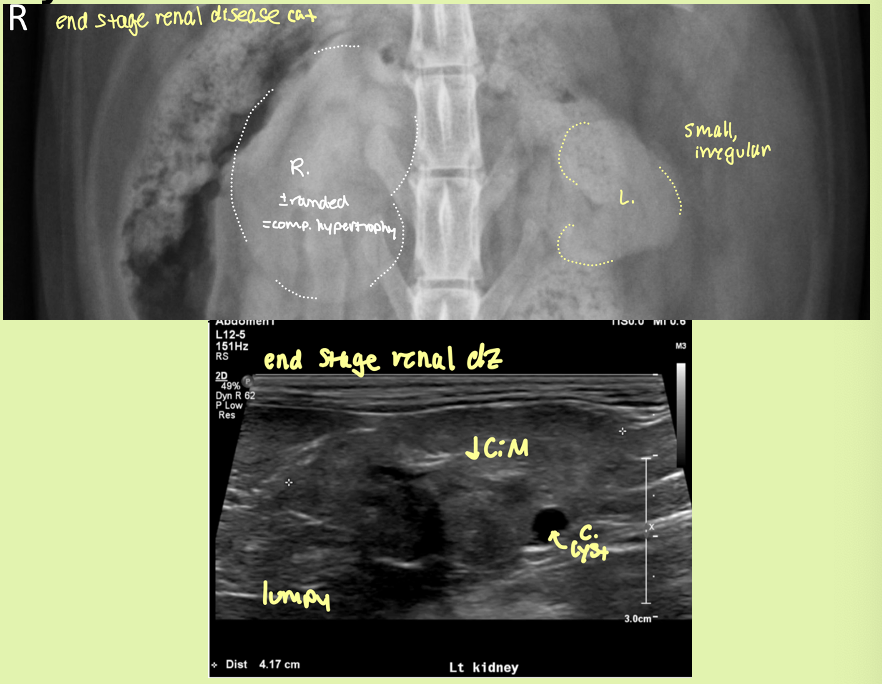

5 reasons for decreased kidney size

chronic inflam

end stage renal disease

infarcts

familial dysplasia, congenital disease

renal hypoplasia

5 focal irregular shape changes kidneys

neoplasia

end stage renal or chronic inflam

renal cysts/PCRD

FIP

condition where one kidney becomes enlarged to compensate for a down kidney

compensatory hypertrophy

kidney preserved architecture

decreased CM distinction

small, irregularly lumpy, bumpy shaped kidneys, ↓CM distinction ± mineralization

end stage kidneys